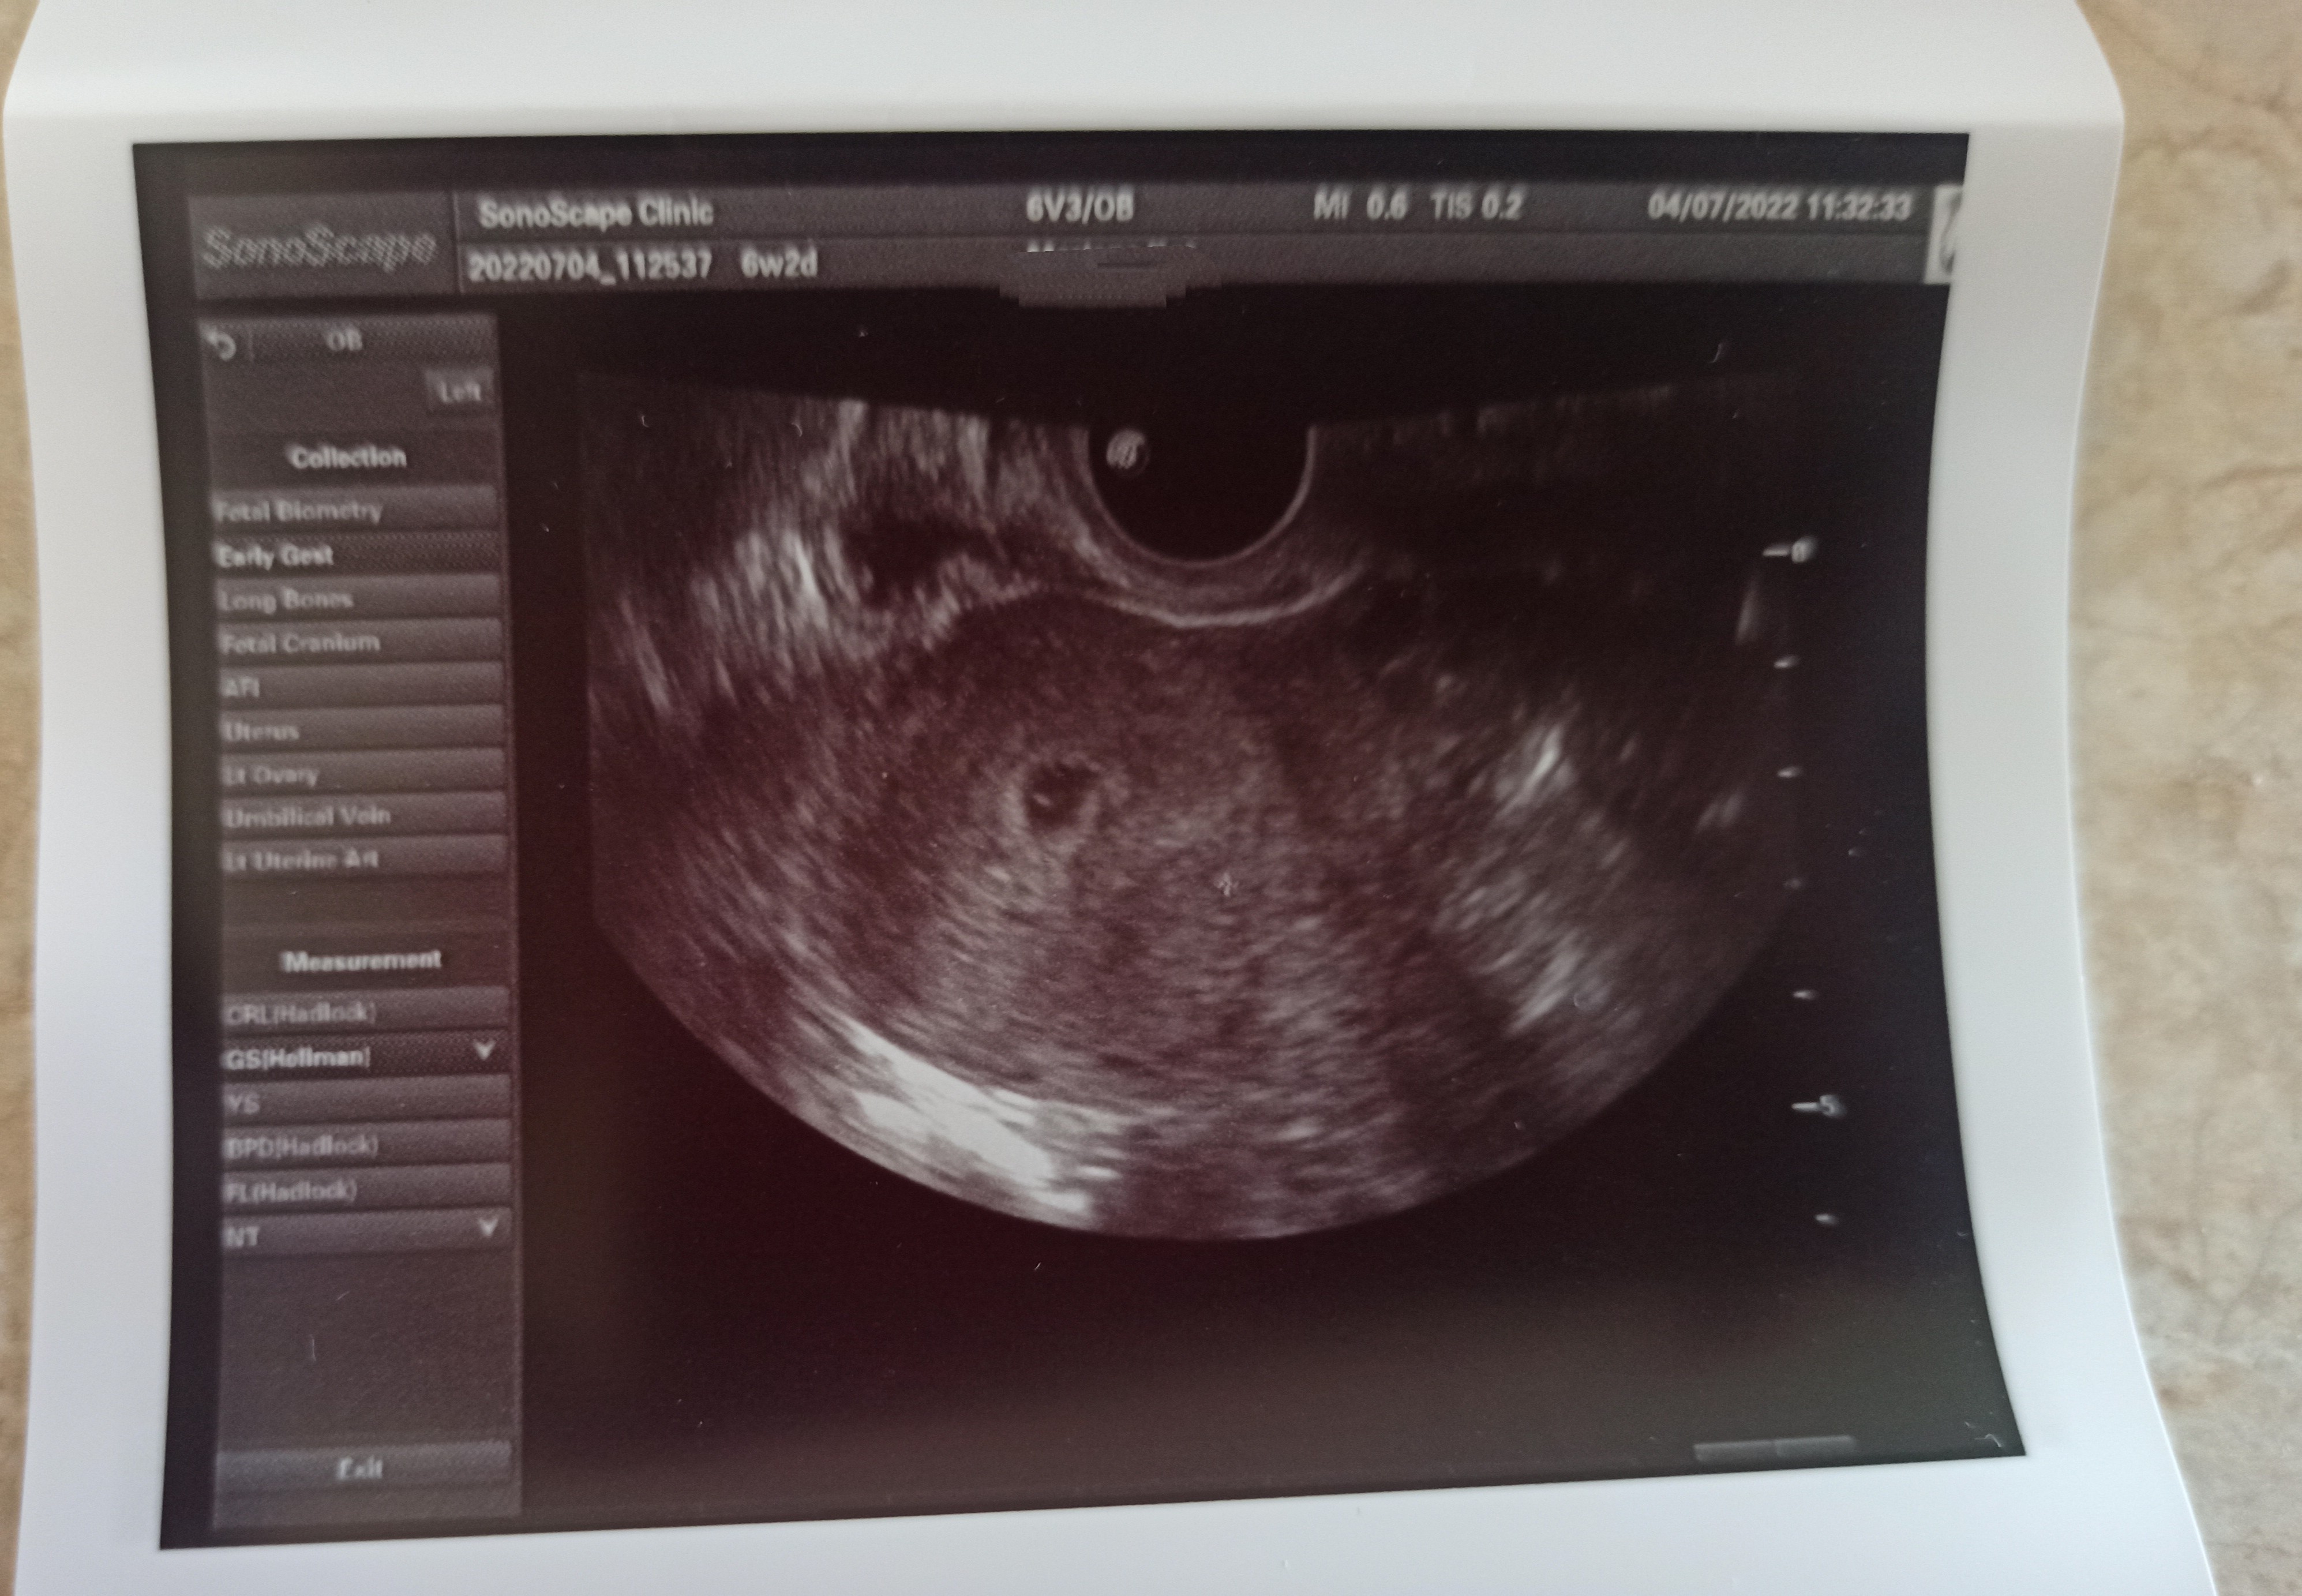

Dziewczyny byłam w pn na USG, lekarz zobaczył pęcherzyk ale serduszka jeszcze nie było słychać mam iść na wizytę 11.07.

Po badaniu dał mi wydruki USG. Dopiero później zaczęła je oglądać i widać tak jakby dwa pęcherzyki?? Co o tym myślicie?

Gdybyś była w ciąży bliźniaczej to lekarz by Ci o tym powiedział, ciąża bliźniaczą wygląda inaczej na usg